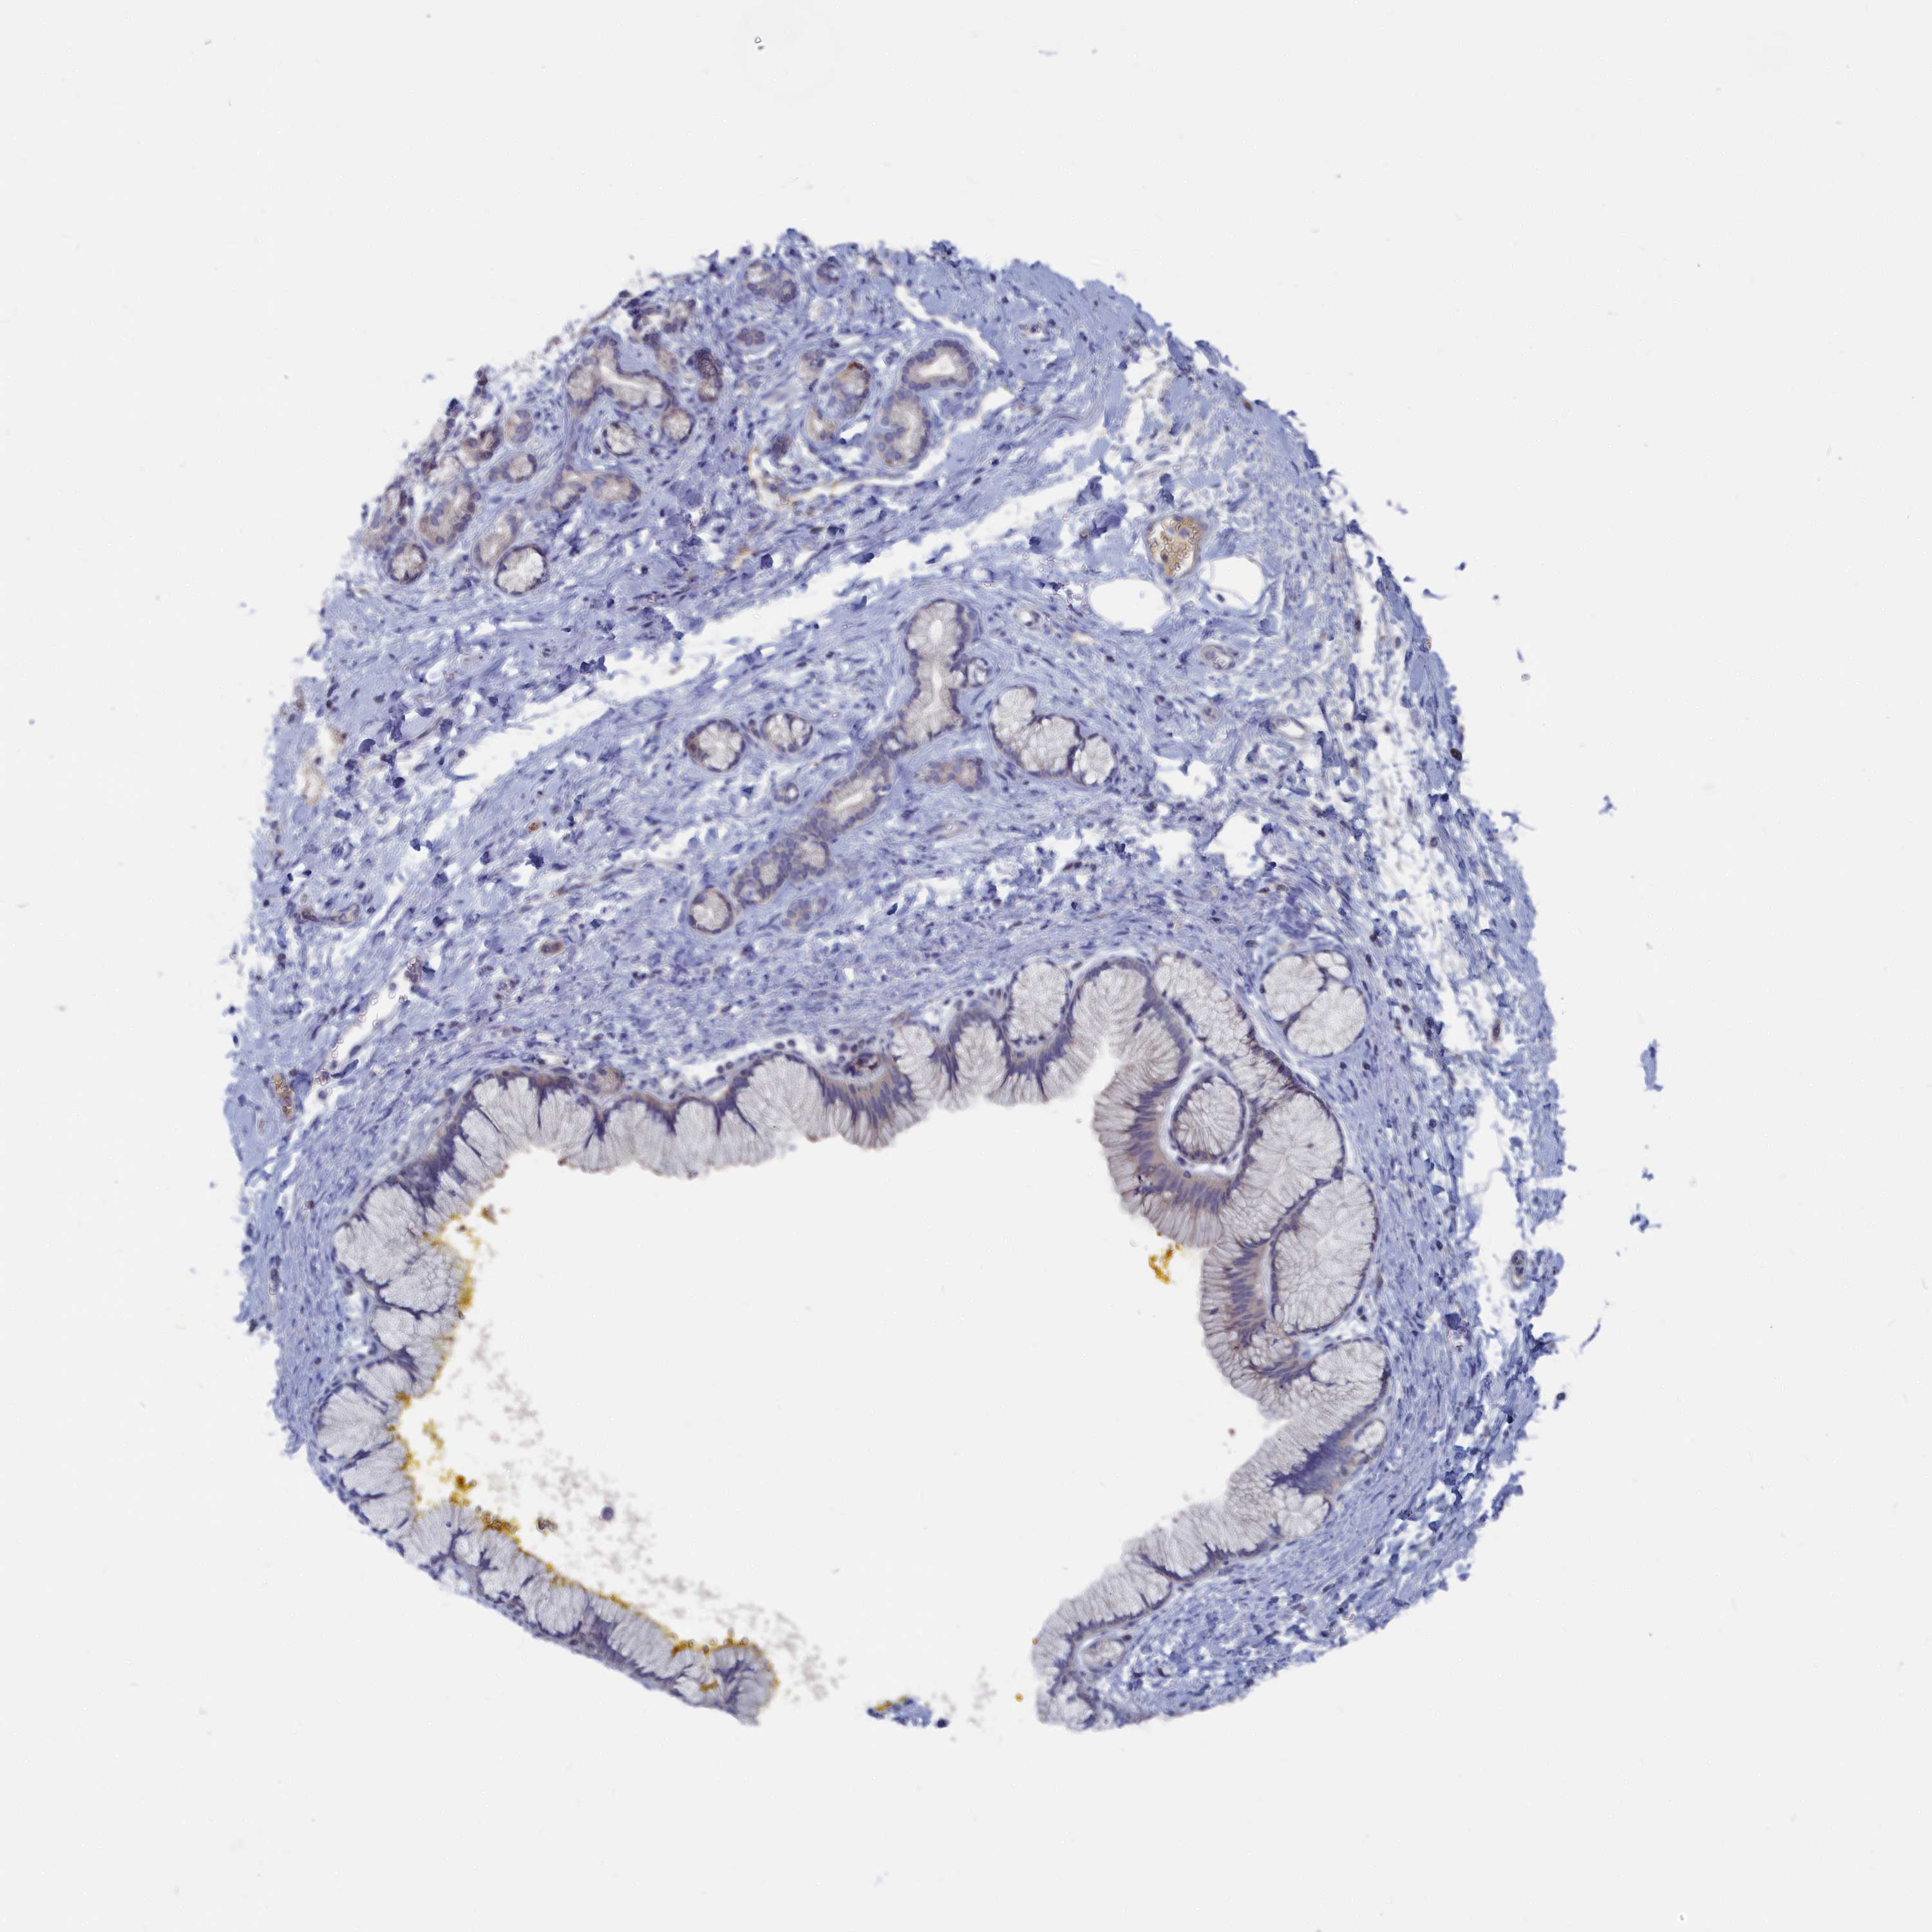

PANCREATIC CANCER - Protein expressioni

A mouse-over function shows sample information and annotation data. Click on an image to view it in a full screen mode. Samples can be filtered based on level of antibody staining by selecting one or several of the following categories: high, medium, low and not detected. The assay and annotation is described here.

Note that samples used for immunohistochemistry by the Human Protein Atlas do not correspond to samples in the TCGA dataset.

Antibody stainingi

Antibody staining in the annotated cell types in the current human tissue is reported as not detected, low, medium, or high, based on conventional immunohistochemistry profiling in selected tissues. This score is based on the combination of the staining intensity and fraction of stained cells.

Each image is clickable and will lead to virtual microscopy that enables deeper exploration of all samples and also displays staining intensity scores, fraction scores and subcellular localization as well as patient and tissue information for each sample.

Antibody HPA042527

Staining

High

Medium

Low

Not detected

Intensity

Strong

Moderate

Weak

Negative

Quantity

>75%

75%-25%

<25%

None

Location

Nuclear

Cytoplasmic/membranous

Cytoplasmic/membranous,nuclear

Adenocarcinoma, NOS